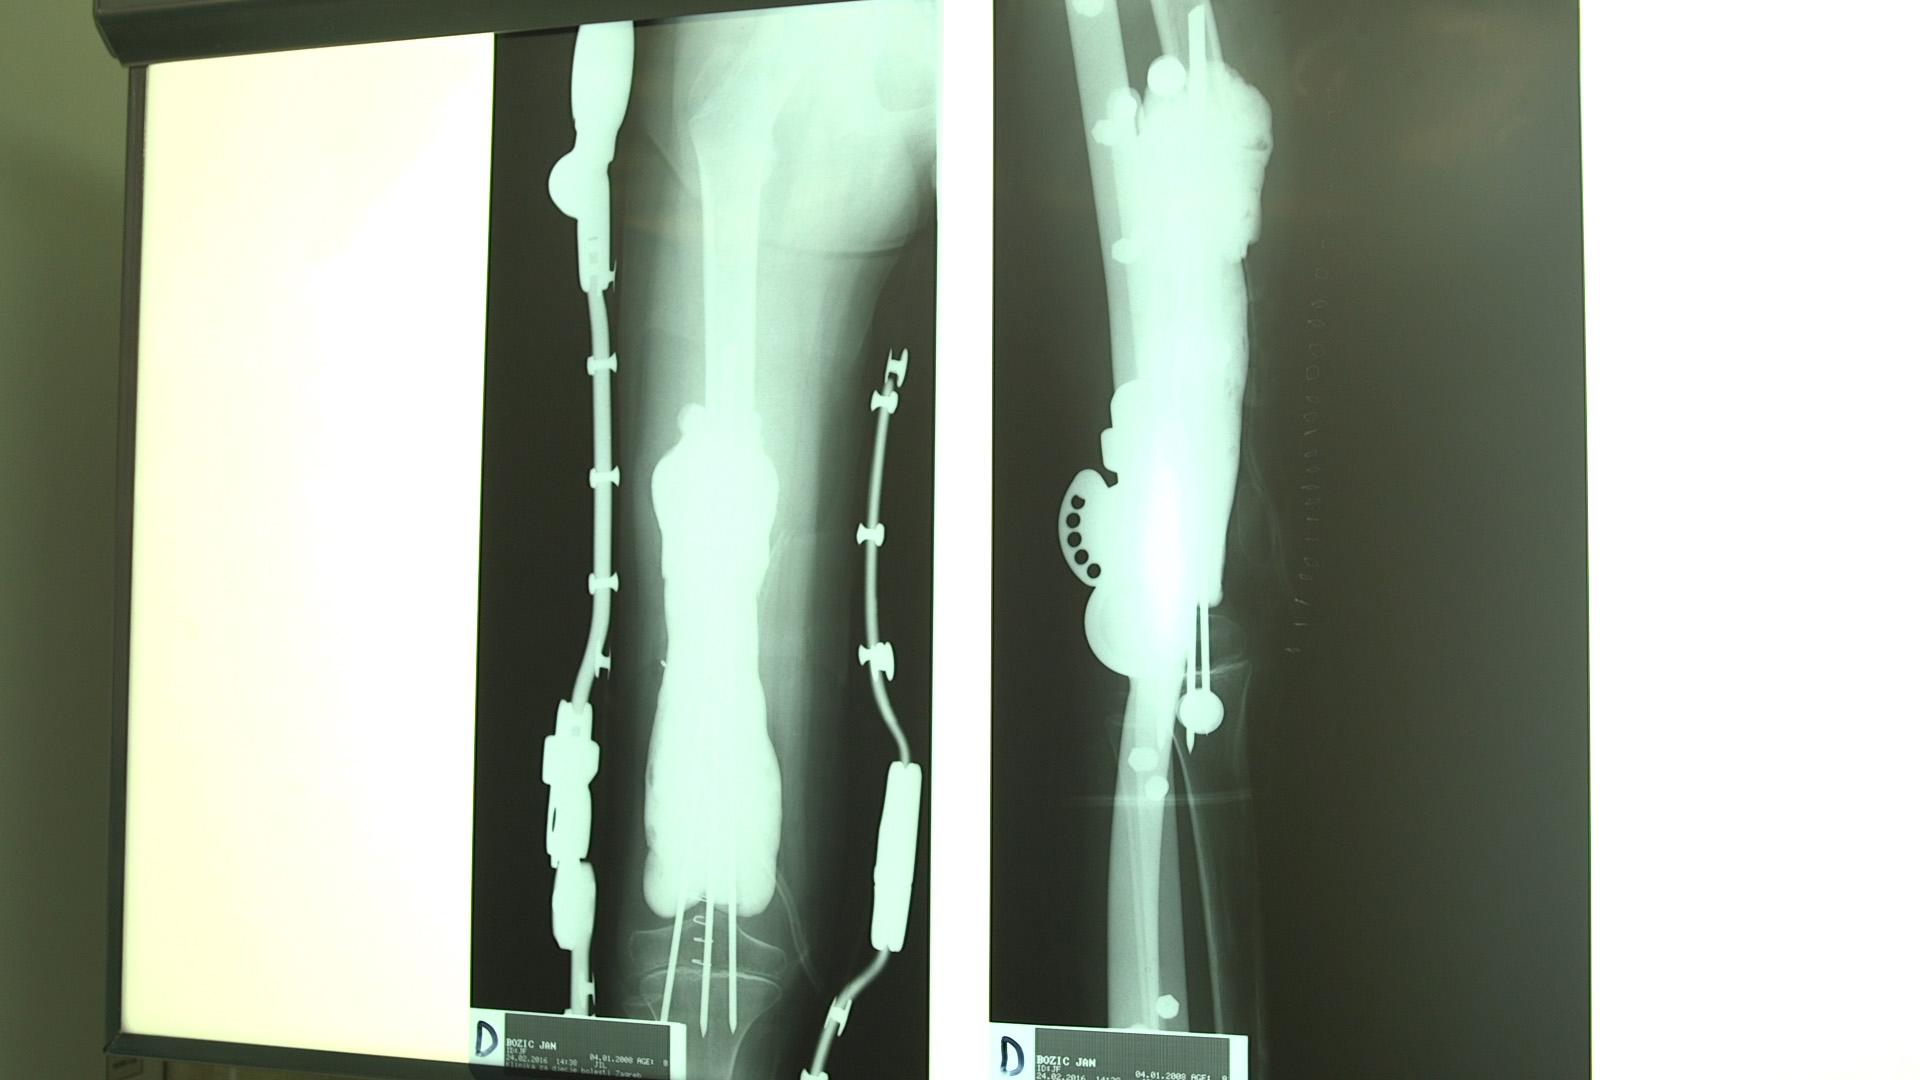

OVO JU JE PROMIJENILO Kuharica Suzy Josipović imala je tumor, a nakon borbe s ozbiljnom bolešću je otkrila: 'Zaboljela me desna ruka'